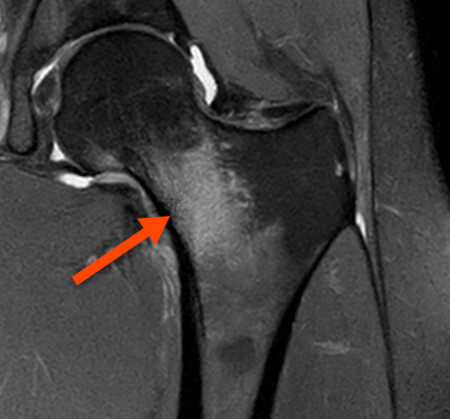

Questo qui sotto, invece, è il collo del mio femore sinistro in un bel “servizio fotografico” che ho fatto la settimana scorsa nella sala di risonanza magnetica dell’ISEH (Institute of Sport, Exercise and Health), qui a Londra 😅

Titolo del “book fotografico”: frattura da stress da compressione di grado 1.